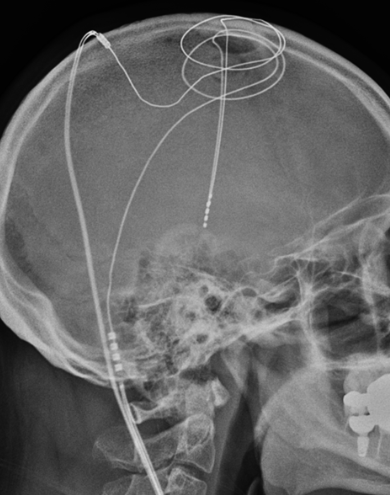

Palpitation